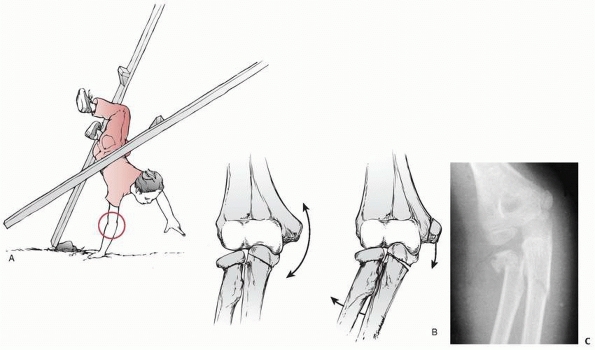

injuries in the elbow region, which depend on whether the bending force

is directed toward varus or valgus. If a child falls with the forearm

in

supination, the carrying angle tends to place a valgus stress across

the elbow. The result may be a greenstick fracture of the ulna with an

associated fracture of the radial neck or avulsion of the medial

epicondylar apophysis (Fig. 11-45). If the fracture involves the radial neck, Bado35 classified it as an equivalent of the type I Monteggia lesion.

FIGURE 11-45 Valgus pattern of an extension fracture. A. A fall with the elbow extended places a valgus stress on the forearm. B.

With increased valgus, a greenstick fracture of the olecranon can occur with or without a fracture of the radial neck or avulsion of the medial epicondylar apophysis. C. Radiograph of a valgus extension fracture of the olecranon with an associated fracture of the radial neck. |